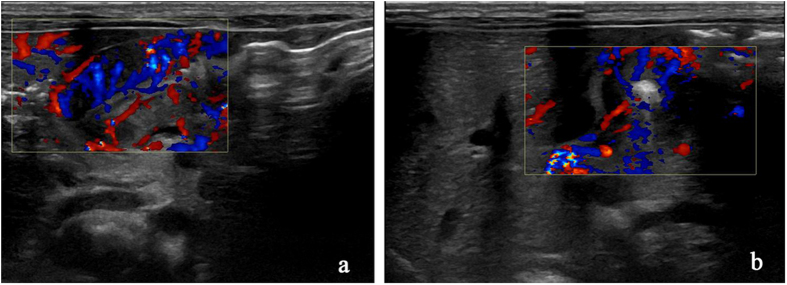

Contrast agent was injected through the stomach tube into the stomach to observe the flow condition in the pyloric canal (Fig. 2). By using color Doppler artifacts technique, the moving condition of contrast agent in the pyloric canal was observed clearly. When the liquid passed from the gastric antrum to the duodenum, color Doppler artifacts showed a mixed stack effect which was obvious and the signal was bright with a colorful flow signal (Fig. 3).

Figure 3.

Doppler artifacts for examining the whole process of color blood flow passing through the Pylorus.

During 20 min observation by CDFI, 10 cases of 65 CHPS infants for the first through time was 5 min, 5–20 min in 25 cases, 30 cases had no obvious liquid through after 20 min. During the observation, liquid passing in 7 cases was observed for more than 3 times, 28 cases for 1–3 times. The mean pyloric diameter was about 1.98 ± 0.33 mm (Table 4).

Our study used color Doppler imaging to observe the condition of contrast agents through the pyloric canal. Together with the experience of domestic and foreign scholars21, 22, color Doppler artifacts can be broadly divided into the following categories: Firstly, there is no color or few color signals were observed in the area of blood flow. Secondly, too many color signals were observed in the blood flow. Thirdly, color signals appeared in the non-blood flow area. Fourthly, color signals or its shades of color change caused the misunderstanding in the direction and velocity of blood flow. In our study, the color signals appeared in the non-blood flow regions. The principle behind this is that it was similar to that of the “flame sign” caused by the spray of the ureteral orifice. It is an artifact that was generated by the rapid flow of liquid, which may be related to the presence of micro materials in the flow of liquid causing ultrasound scattering23, 24. In the planar ultrasonic condition, it is sometimes difficult to catch the movement of contrast agents through the pyloric canal because of the contrast echoes produced by the liquid as well as pyloric canal were not strong, which cannot reflect the pyloric stenosis objectively and may be misleading clinically. Using color Doppler artifacts, we can dynamically observe the whole process of liquid passing through the pyloric canal more intuitively, the time and frequency of liquid that passes into the stomach through the pyloric canal, and also measure the pyloric length, which in turn provides an objective basis for the clinical evaluation of hypertrophic pyloric stenosis.